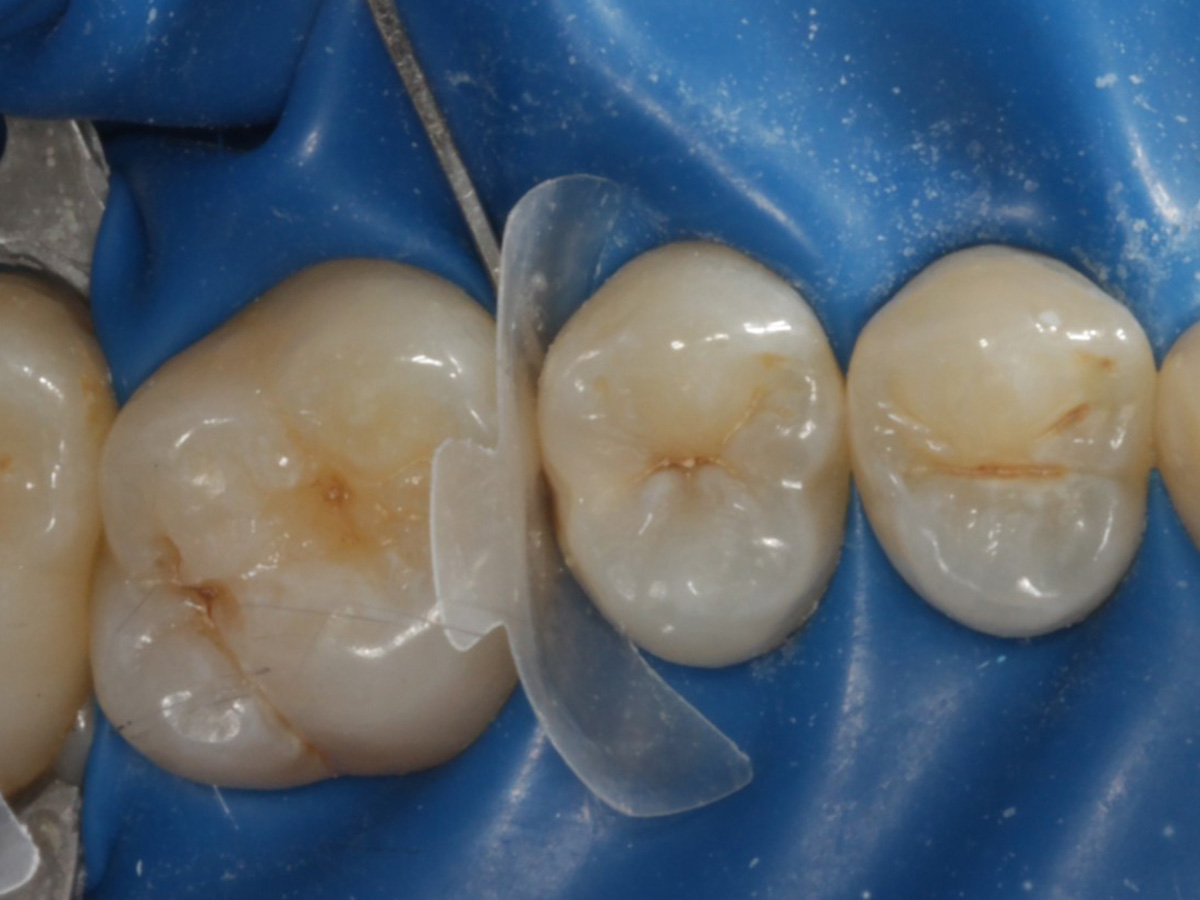

Abbildung 18

Fertige Restauration